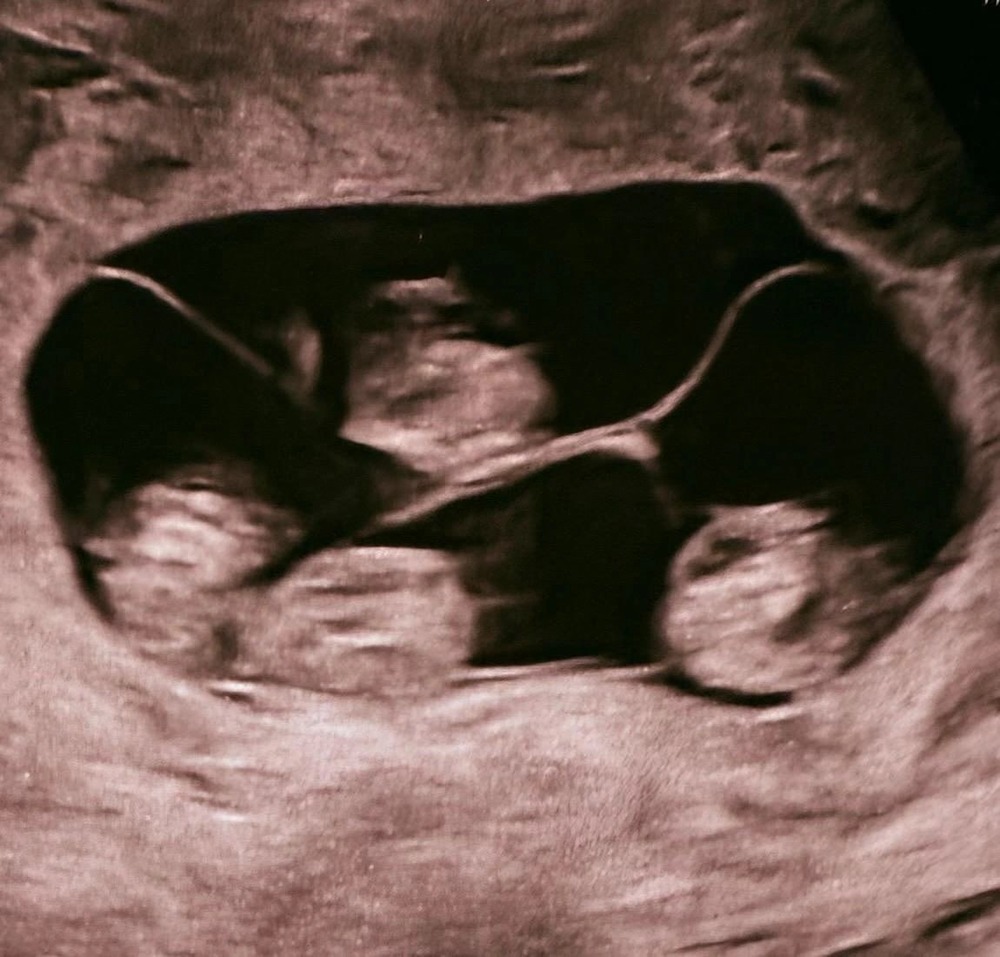

Впервые в России женщина родила однояйцевую четверню. Такое происходит 1 раз в 15,5 млн родов

⚡️ Впервые в России женщина родила однояйцевую четверню. Такое происходит 1 раз в 15,5 млн родов. Все четверо — неотличимые девочки-близнецы. Вес новорождённых малышей из Питера от 1360 до 1640 г, а рост — от 37 до 41 см. Всего в мире насчитывается около 15 идентичных четверняшек, причём 10 из них — девочки.